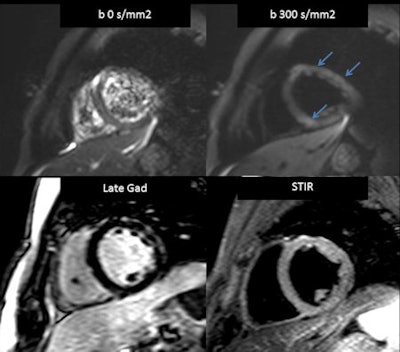

Acute myocarditis seen at (clockwise from upper left), low b value MRI, high b value MRI, short-tau inversion recovery (STIR), and late gadolinium enhancement (LE). All images courtesy of Dr. Jordi Broncano.Black blood STIR images deliver moderate sensitivity for edema in the setting of acute myocarditis: 45% to 100% sensitivity, 50% to 100% specificity, 59% to 79% accuracy overall, he said. The aim was to assess the clinical feasibility of whole cardiac high b value DWI of myocardial edema in acute myocarditis compared with standard [cardiac MR] techniques, Broncano said.

Rather than the standard black blood STIR protocol, the researchers pioneered a high b value DWI protocol to detect edema in patients with acute myocarditis.

They found no significant differences in the results between STIR and DWI, but slightly higher sensitivities and positive predictive values for the latter. And the effects of edema on the myocardium were much more conspicuous on the DWI protocol, earning the new technique slightly better results overall.

"Both STIR and DWI with late gadolinium enhancement showed high sensitivity and positive predictive value for both readers, with excellent interobserver agreement," Broncano said. "No significant variations were observed in the extent of myocardial edema between the STIR and DWI, although the conspicuity of affected myocardium was greater on the DWI."

Using late gadolinium enhancement (LGE) as a reference standard, results showed that sensitivity and positive predictive value were slightly, but not significantly higher in DWI versus black blood STIR images(right).